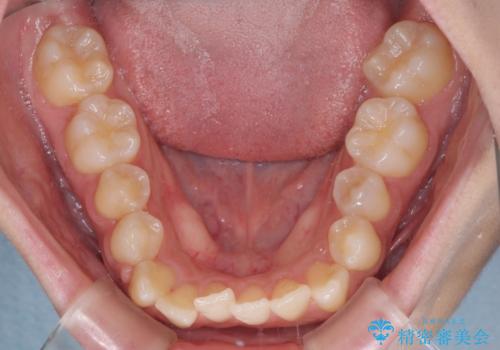

- 上下のデコボコと奥歯の咬みにくさを気にして来院された患者様です。

上顎骨の幅が下顎骨よりも小さく受け口傾向であったため、拡大装置により上顎骨の骨幅を広げて上下関係を改善し、その後インビザラインにて歯並びを整えることとしました。

下顎歯列は上顎歯列内に収まるように並んでいますが、上顎骨の幅が狭いと、下顎臼歯が全体的に舌側に傾斜した歯列となってしまいます。

舌側に傾斜した歯列は奥歯に力の負担がかかりやすく、歯磨きがしにくいなどの問題があるため、上顎骨拡大により舌側傾斜を改善することが可能となります。